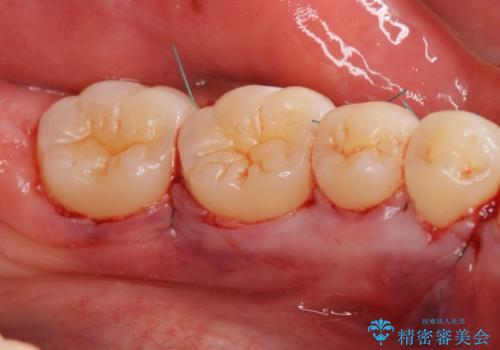

- 舌が下顎の骨隆起にあたって不快との事で来院。

静脈内鎮静麻酔を行い下顎骨隆起切除術を行いました。

骨隆起がなくなり舌が当たるストレスがなくなり大変満足していただけました。